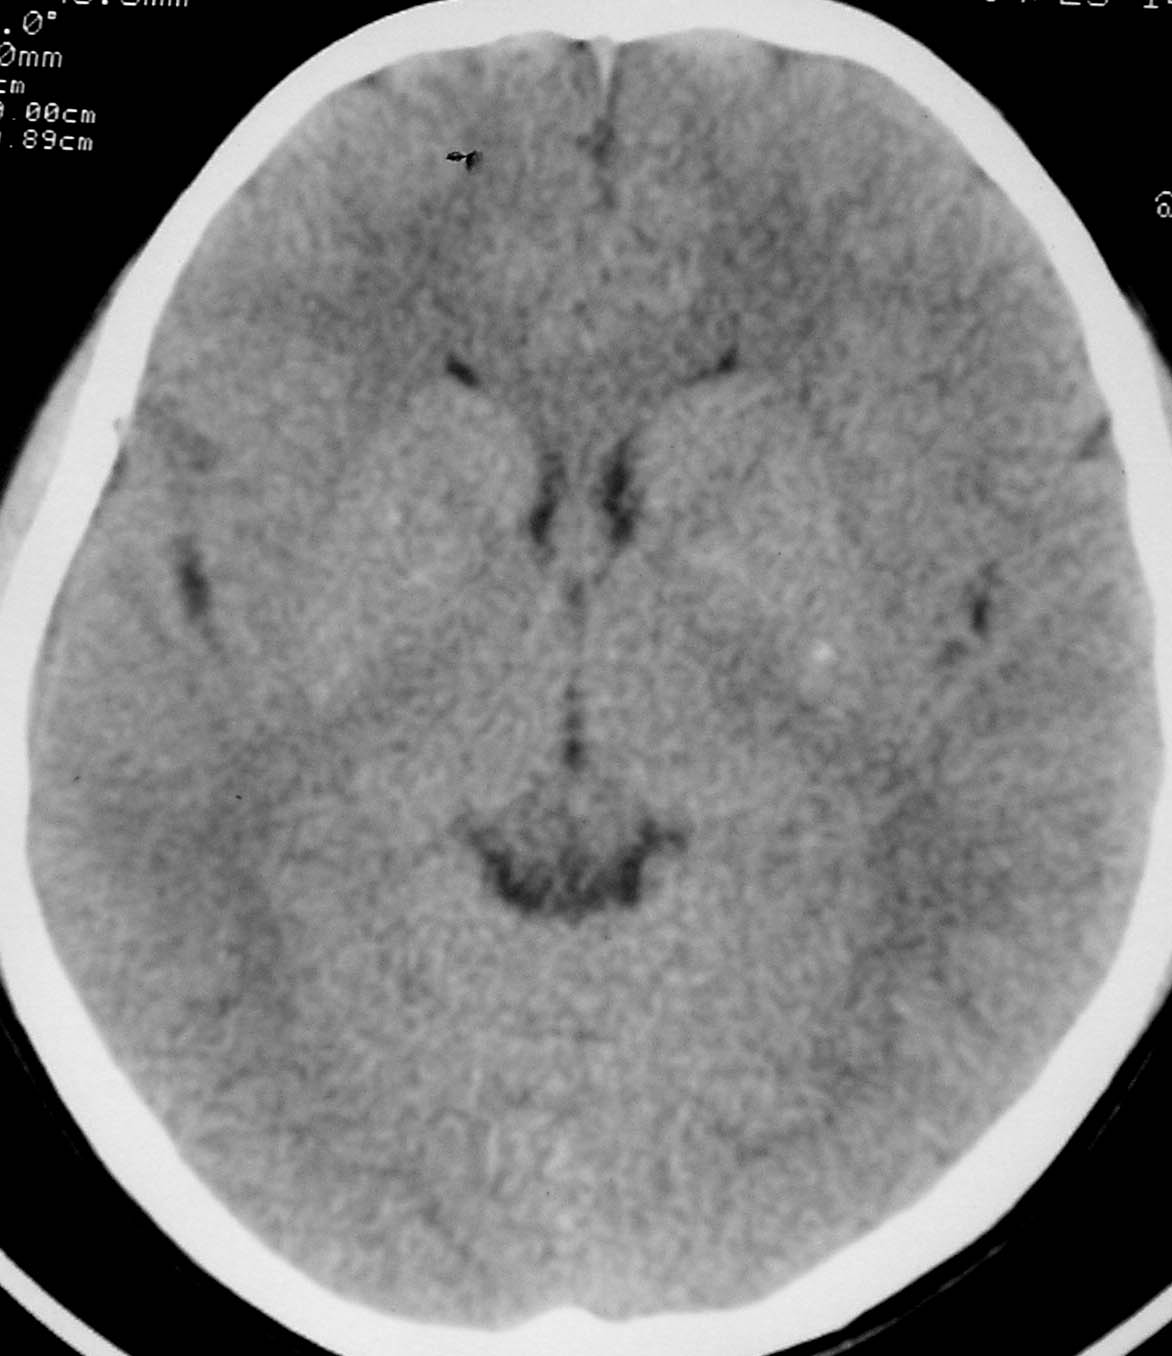

以下是引用余辉在2007-4-28 19:55:00的发言:[br]血管畸形?增强一下

以下是引用jw-830在2007-4-28 20:22:00的发言:[br]考虑血管畸形可能建议增强

以下是引用ysxyy在2007-4-29 21:14:00的发言:[br]像是假像,如果不放心可以偿试一下:[br]你用听眦线为基线扫一下,再用听眶线扫一下,就是说用不同的角度扫同一个地方;[br]看看有无变化,是不是有相同或相似的表现,即可鉴别;